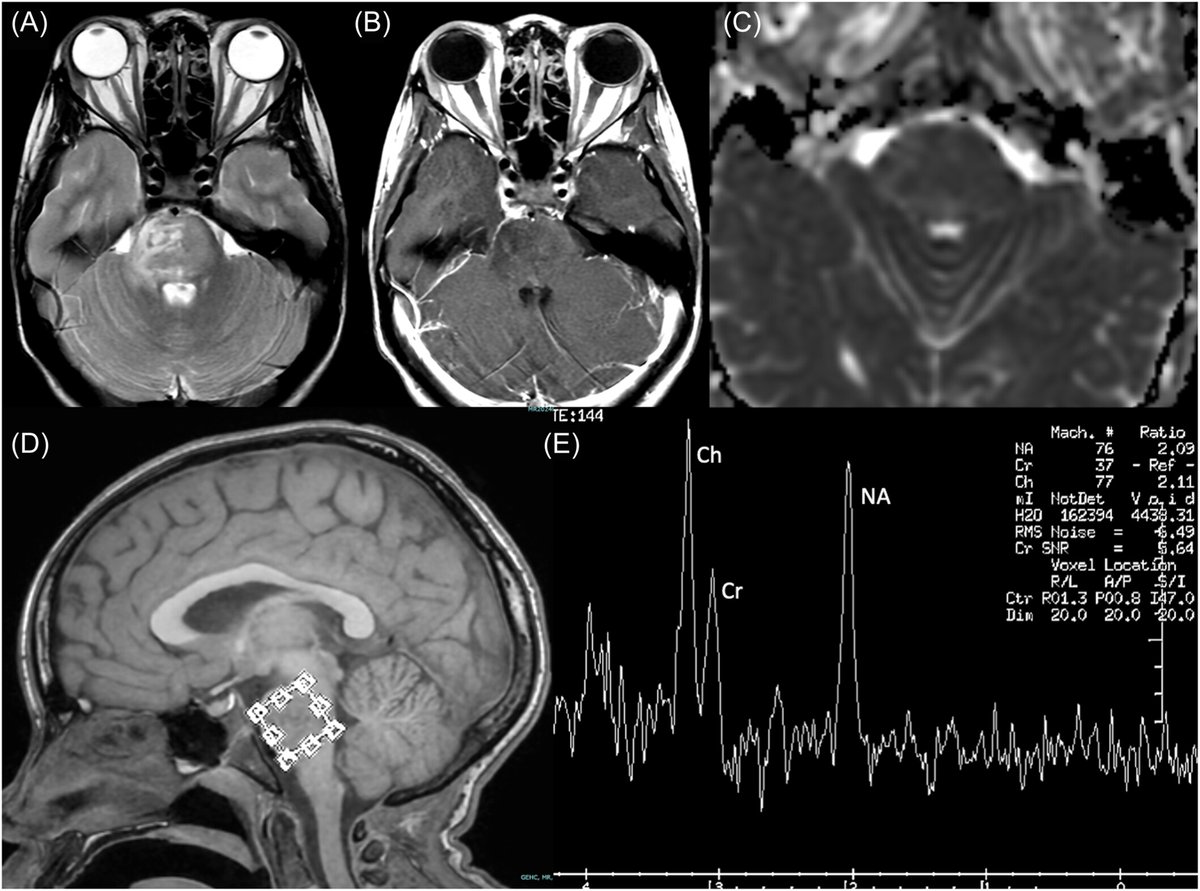

Vivien X. Xie & colleagues at Children's National Hospital šŸ„ present a novel example of pediatric NMOSD & autoimmune GFAP astrocytopathy overlap syndrome originally presenting as an infiltrative pontine mass. Read more for free: onlinelibrary.wiley.com/doi/10.1002/cn… @WileyNeuro Ben Siegel #neuroimmunology

Vivien X. Xie &amp; colleagues at <a href="/ChildrensNatl/">Children's National Hospital šŸ„</a> present a novel example of pediatric NMOSD &amp; autoimmune GFAP astrocytopathy overlap syndrome originally presenting as an infiltrative pontine mass. Read more for free: onlinelibrary.wiley.com/doi/10.1002/cn…

@WileyNeuro <a href="/BenSiegelMD/">Ben Siegel</a> #neuroimmunology